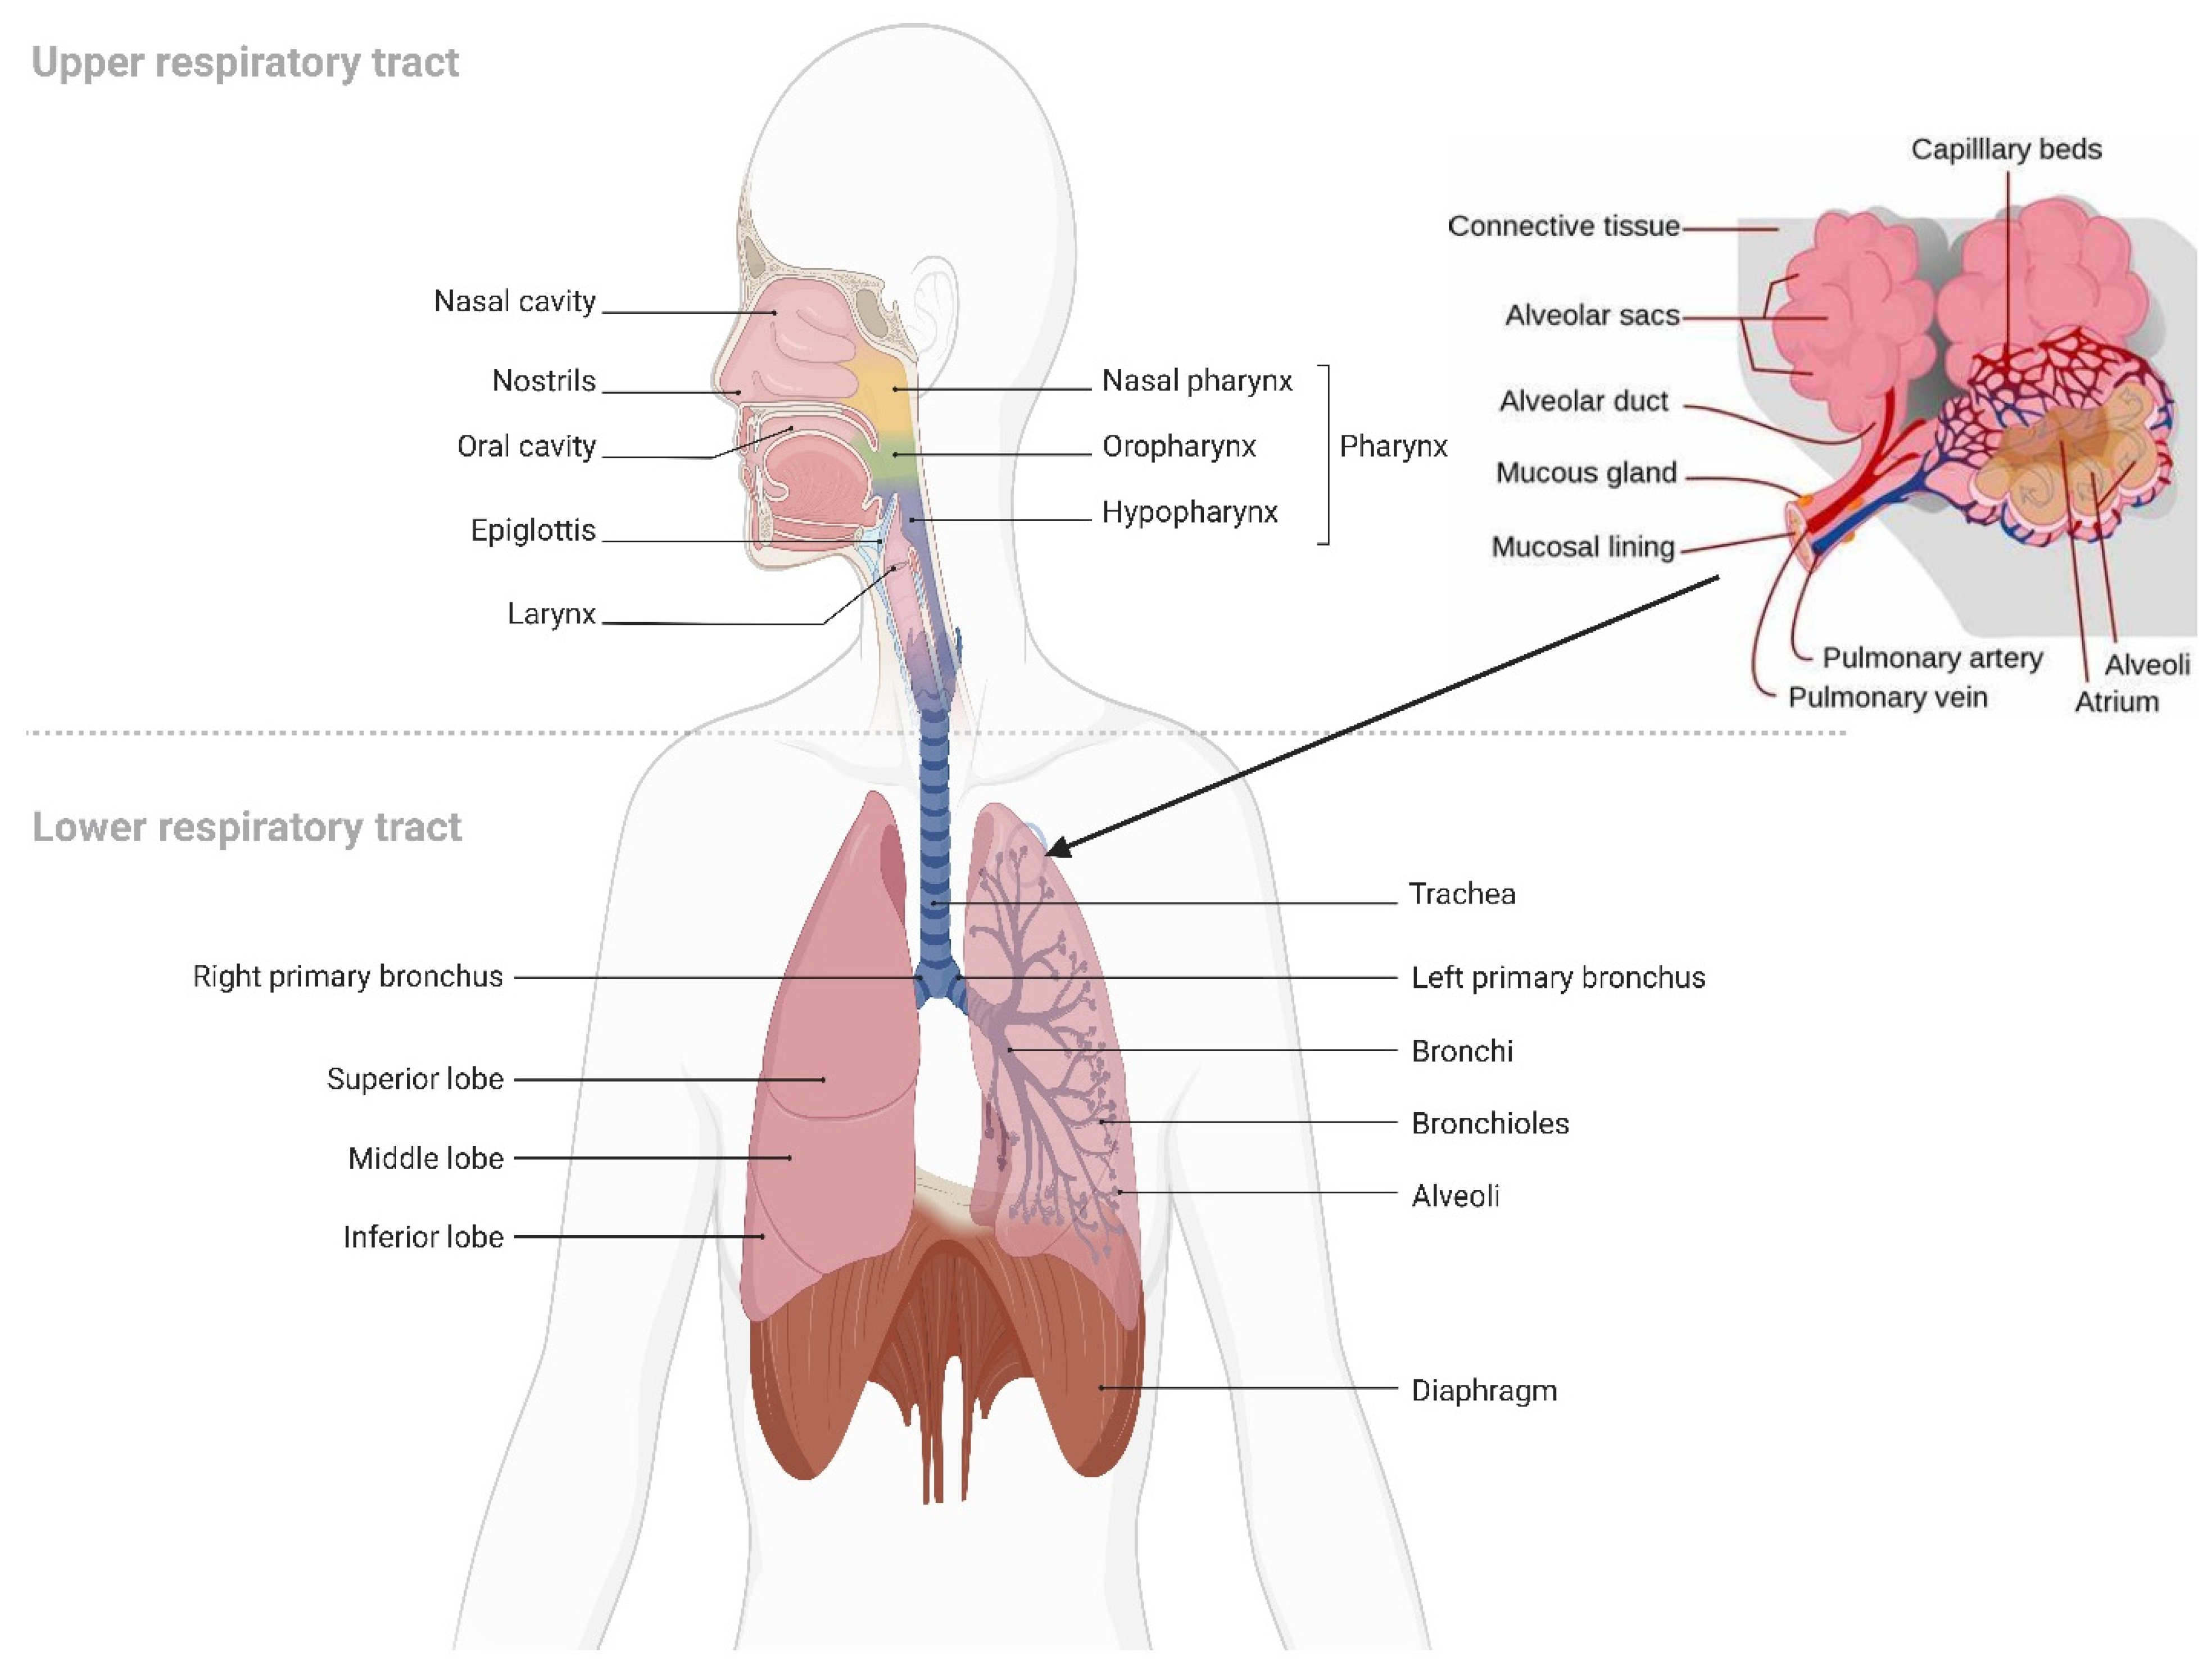

5. Pulmonary Drug Delivery

5.1. Overview of Pulmonary Drug Delivery

5.2. Requirements for Pulmonary Drug Deep Deposition

5.2.1. Inhaled Drug Formulation

Particle Size and Deposition Pattern